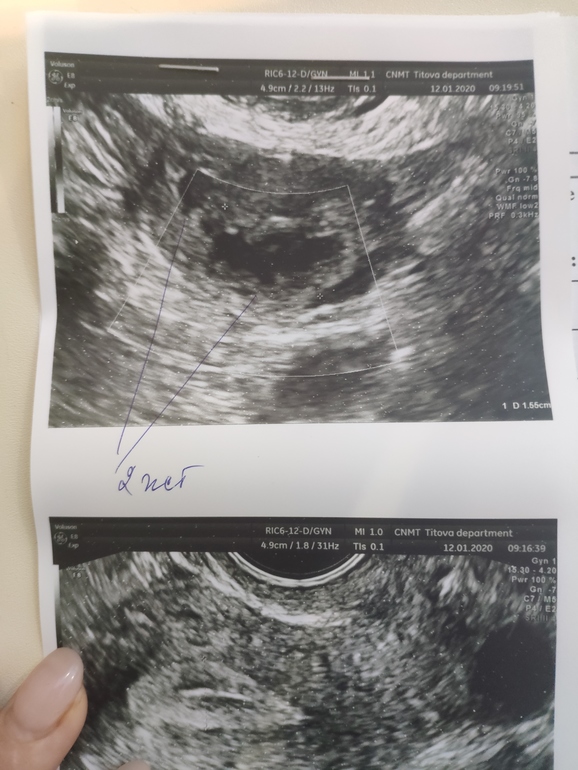

2 жёлтых тела, у кого было?

ФолликулометрияДевочки, может второе, это с прошлого цикла? Но почему у него тогда кровоток есть🤷 Доминантный фоликул вроде один был.

Двойная овуляция явление не редкое. У меня было 2 с разницей в 4 дня. Вторую поймали, вот, и держим)))

Значит совулировали два фолликула. Бывает что на узи увидели большой один, а к моменту овуляции подоспел и второй